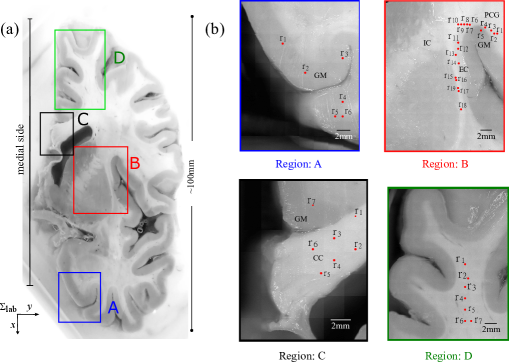

Figure 1: (a) Photograph of a coronal cross section of a healthy human brain fixed in 4%percent44\% formaldehyde solution. The regions marked in different colors were probed in this study. The medial side of the brain was aligned parallel to the x-axis in the output coordinate system (outsubscript𝑜𝑢𝑡\sum_{out}). (b) shows zoomed in images of the regions marked as A, B, C and D in (a). The red points illustrate the illumination spots of the probing beam (measurement points risubscriptr𝑖\textbf{r}_{i}). GM: Gray Matter, CC: Corpus Callosum, EC: External Capsule, IC: Internal Capsule and PCG: Pre-Central Gyrus.

Fig. 1(a) shows a coronal section of a healthy human brain (anonymous donor). The sample was obtained during autopsy and was fixed in neutral buffer formalin (4%percent44\% formeldehyde) solution. For our investigation, we have selected distinct areas within this section: A, B, C and D. The corpus callosum (region C) consists of commissural fibers that connect the left and right hemisphere of the brain. The corpus callosum is the largest fiber tract system in the brain, along its axis all the fibers are aligned. The external capsule, a thin elongated structure (region B), consists of projection fibers connecting the frontal lobe and the spinal cord, as well as to a lesser degree of association fibers that interconnect the frontal and the parietal cortex. Inside the external capsule, a distinct orientation of fibers along the axis of this elongated structure is thus found. Whereas the corpus callosum and the external capsule each represent a well-aligned fiber system, the white matter inside the gyri contains connections to various parts of the brain and thus a mixture of U-fibers, association, commissurial and projection fibers. This results in fibers aligned at different depths in different directions and often over several levels with a mean fiber orientation towards the center of the brain [46]. The superior frontal gyrus (region D) was chosen to showcase this situation. Whereas region B to D were chosen to allow the investigation of distinctive features of fiber alignment in white matter, we additionally selected region A to investigate the response of gray matter.